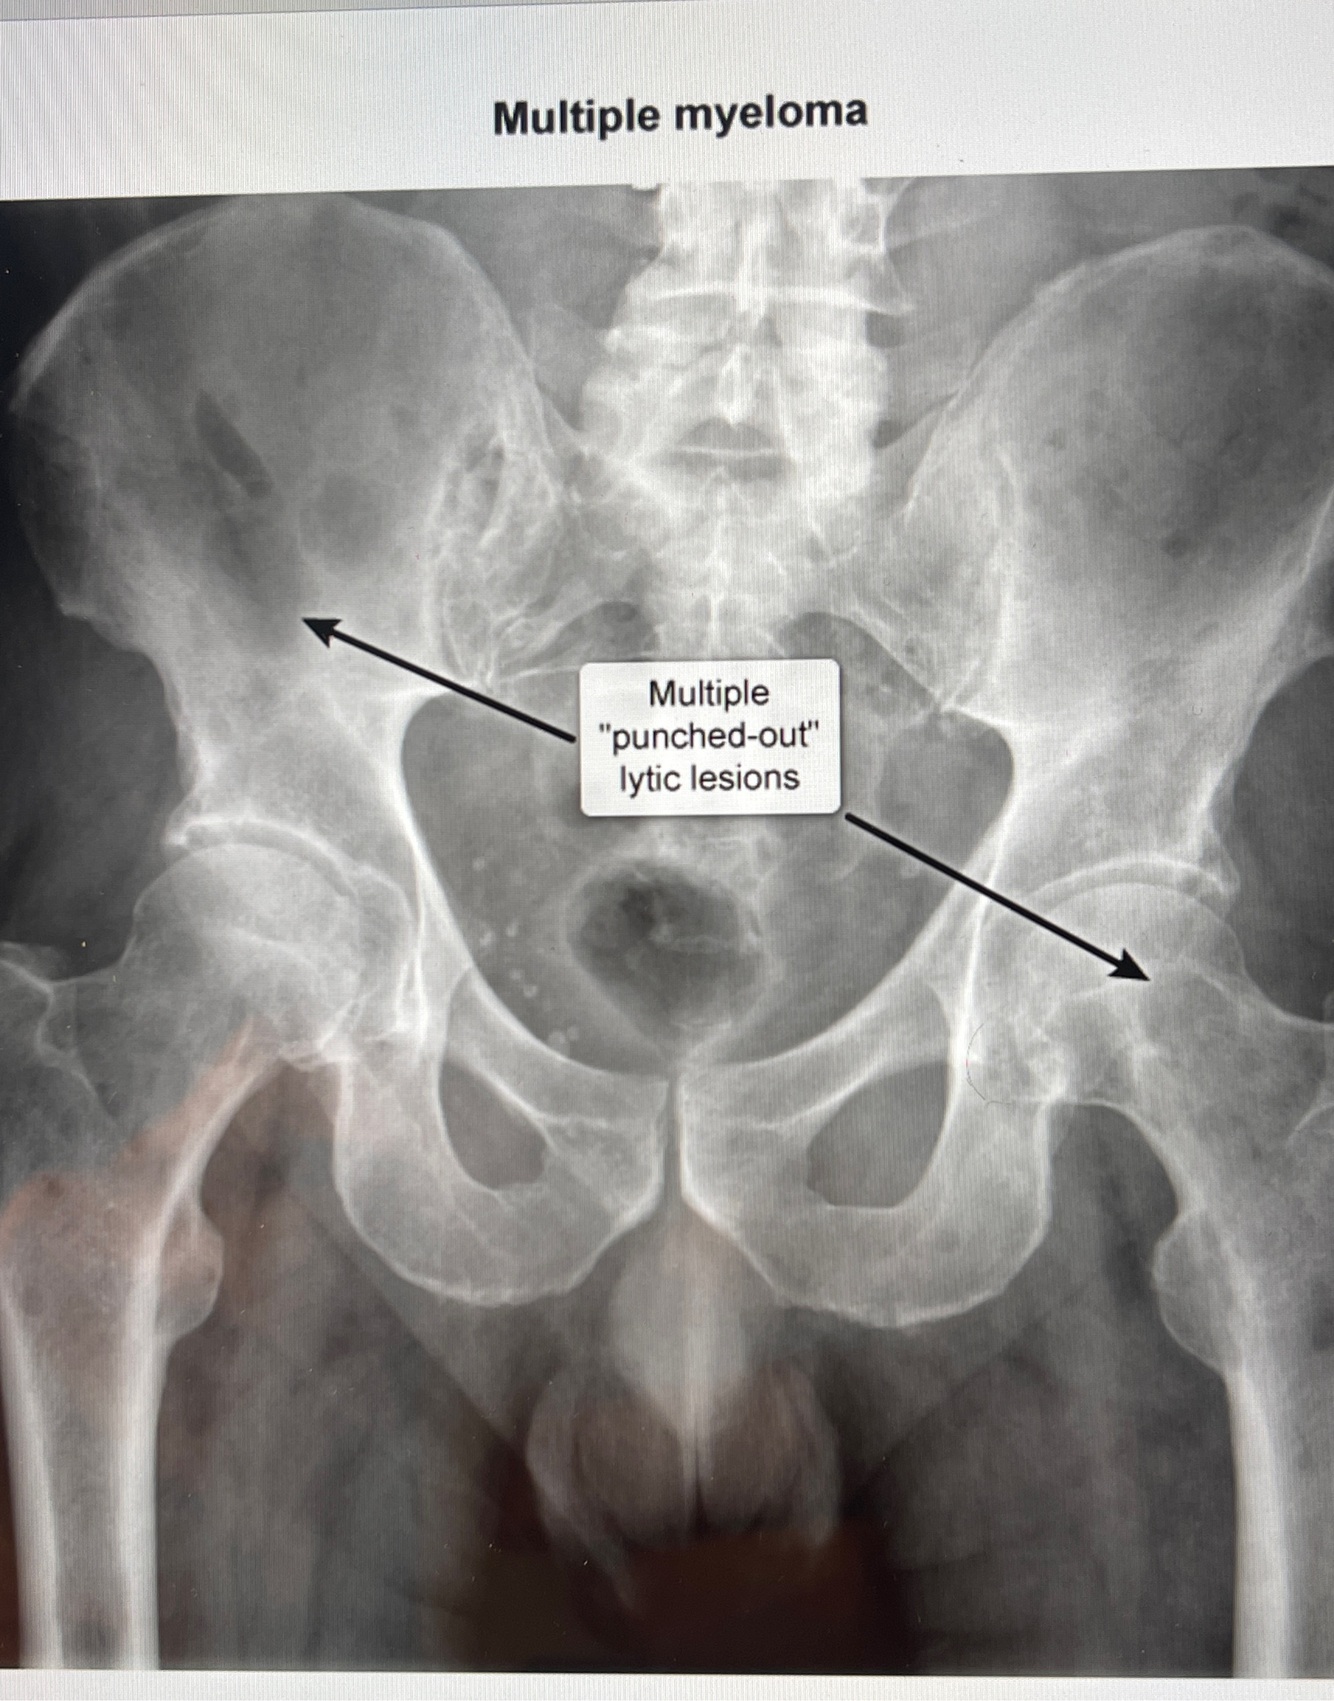

How well did you know this?